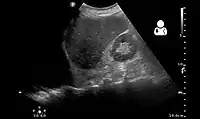

Ultrasound scan of the chest showing a left-sided hemothorax

Ultrasonography may be used to detect hemothorax and other pleural effusions. This technique is of particular use in the critical care and trauma settings as it provides rapid, reliable results at the bedside.[23] Ultrasound is more sensitive than chest x-ray in detecting hemothorax.[25] Ultrasound can cause issues in people who are morbidly obese or have subcutaneous emphysema. When CT is unavailable in the current setting or the person cannot be moved to the scan, ultrasound is used.[3]